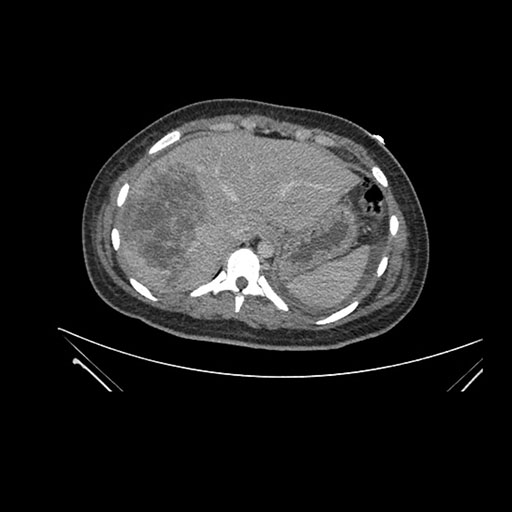

Imaging Analysis

Look through the patient's CT scan to identify any areas of concern for the necessary procedure.

Axial Venous

Based on initial findings, which issue(s) would you be most concerned about?